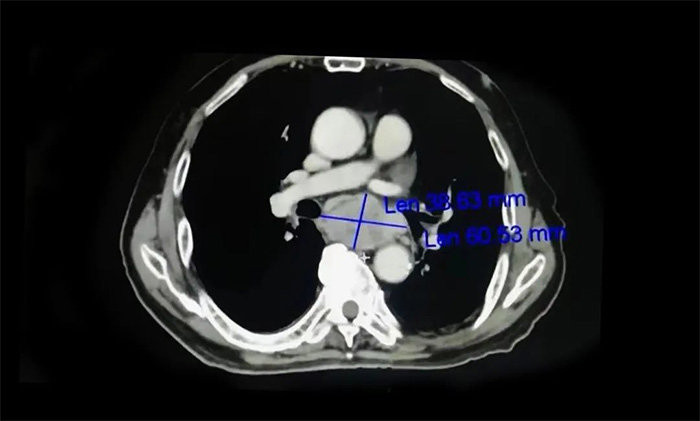

需要提醒的是,食道癌早期患者在就醫(yī)時(shí)常主訴“嗓子處有東西”,這和臨床上常見的咽炎癥狀相似,兩者需進(jìn)行鑒別,要根據(jù)患者病史、癥狀、體征、食管鏡檢查、影像學(xué)檢查結(jié)果等進(jìn)行綜合判斷。其中,食管鏡檢查加活檢病理檢查對(duì)診斷是否患有食管癌具有重要意義,影像學(xué)檢查則可為評(píng)估腫瘤分期提供可靠的依據(jù)。

▲ 影像學(xué)檢查為評(píng)估食管癌分期提供依據(jù)